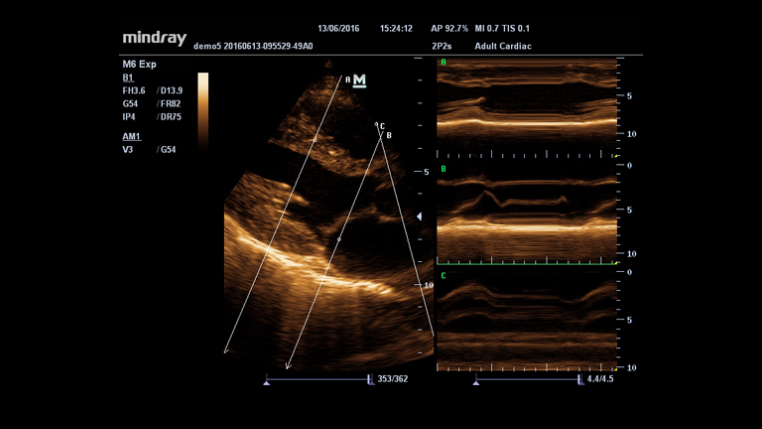

iTouch? (automatyczna optymalizacja obrazu)

Funkcja ta pozwala uzyska? natychmiastow? automatyczn? optymalizacj? obrazu w trybach B, Kolorowego Dopplera i PW (Spektralnego Dopplera Fali Pulsacyjnej) poprzez naci?ni?cie jednego klawisza.